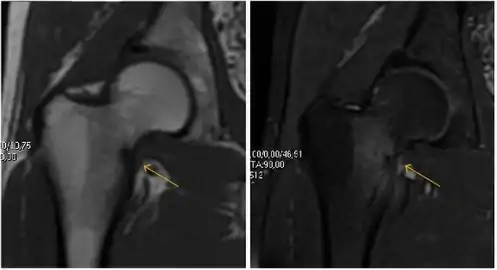

MRI has been shown to have 100% sensitivity and specificity in prospective studies of occult hip fractures. These fractures were diagnosed by bone marrow edema and a low signal fracture line, mainly on T1 or T2 weighted images (Figure 10).[1]

Figure 10:

- Stress femoral neck fracture in a young athlete barely visible in X-ray film as a sclerotic line (arrow)[1]

- In this case, Tc 99 scintigraphy shows a band of uptake[1]

- Furthermore, T1 (left) and DP fat saturated (right) weighted MR images showed the fracture line and a pattern of edema.[1]